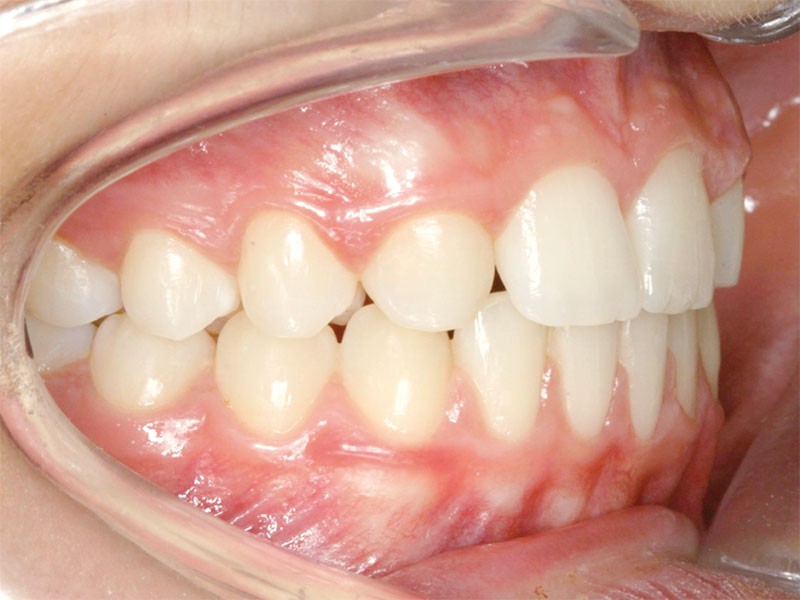

Le traitement orthodontique sans extraction à l’arcade mandibulaire a permis d’établir une occlusion de classe II thérapeutique équilibrée et un sourire harmonieux (fig. 4 et 5).

Une discrète coronoplastie par soustraction a adouci les contours des pointes cuspidiennes canines.